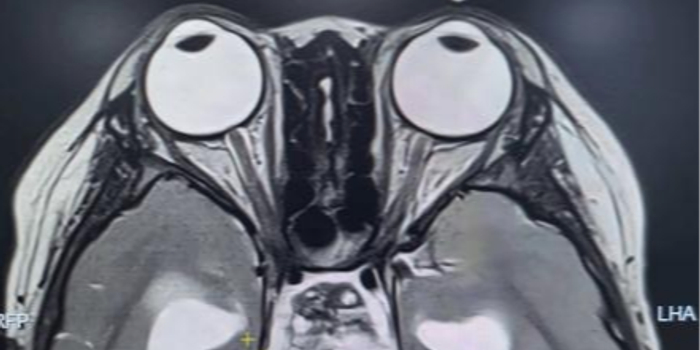

术前核磁共振检查

为精准掌握肿瘤情况,团队为欢欢完善了垂体MRI平扫+增强检查及相关激素水平检测。结果显示:肿瘤体积超过4厘米,形如鸡蛋,已严重压迫视神经与垂体,突入第三脑室,并与周围重要神经血管结构紧密粘连。颅咽管瘤是一种起源于颅底的先天性良性肿瘤,因体积大、位置深,且毗邻下丘脑、视神经、垂体等重要结构,手术切除难度极高,稍有不慎就可能导致失明、终身内分泌紊乱甚至有生命危险。